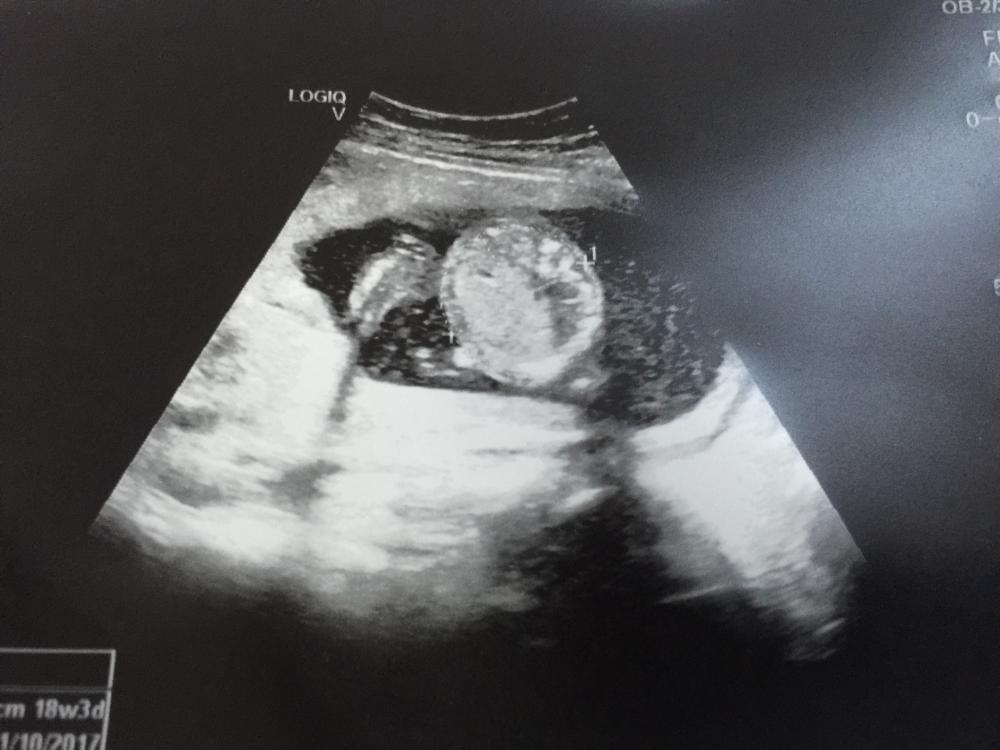

السلام عليكم اللي عندهم خبرة ب السونار